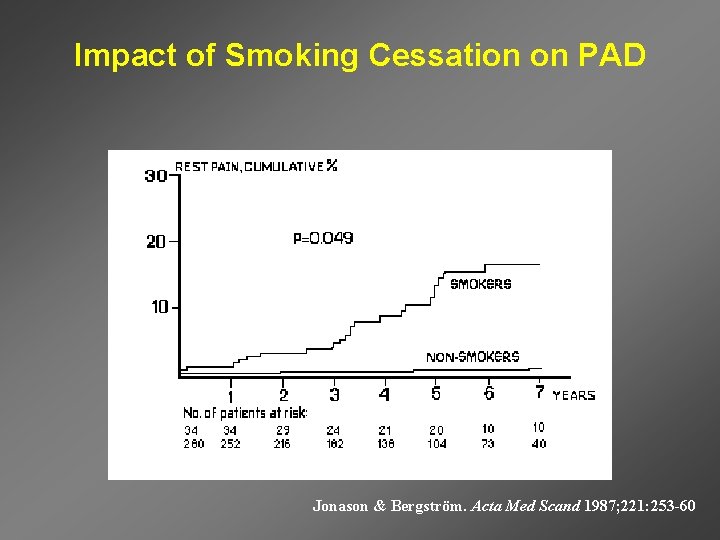

Impact of Smoking Cessation on PAD Jonason & Bergström. Acta Med Scand 1987; 221: 253 -60